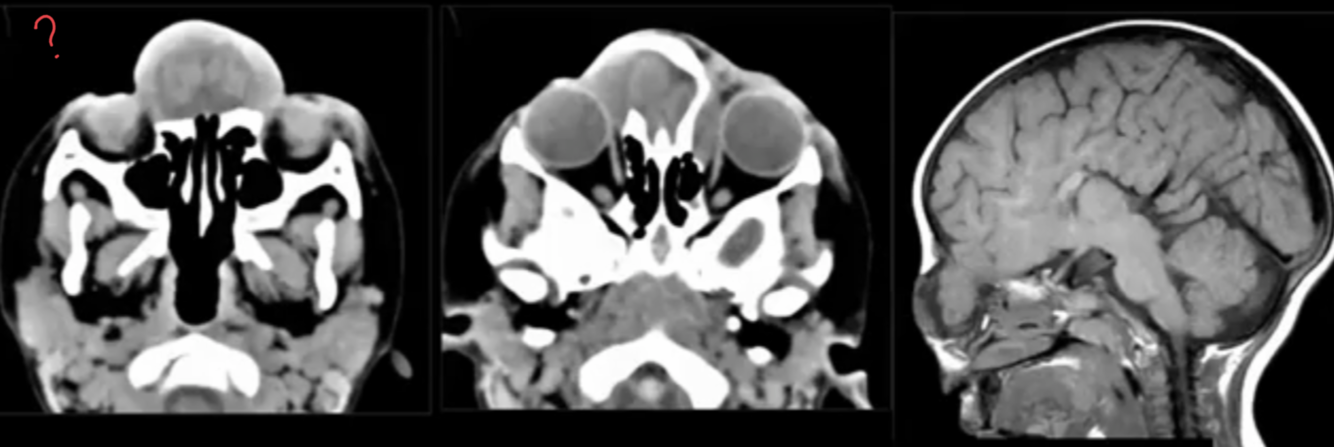

Major points of Encephalocele?

?

Fronto-ethmoidal Encephalocele.

Brain abnormalities possibly associated with Encephalocele?